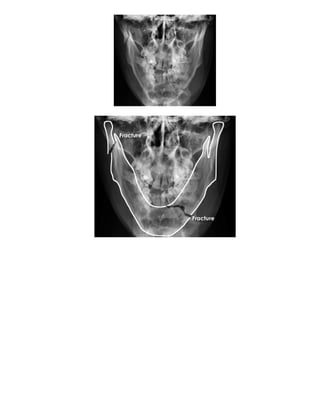

Vôùi phaàn soï maët : Quan saùt xem coù gaõy caønh haøm treân hay döôùi ?

Quan saùt coù coù beå cung goø maù ?

Quan saùt xem coù vôõ xoang traùn ?

Moät soá hình gaõy vuøng haøm maët :